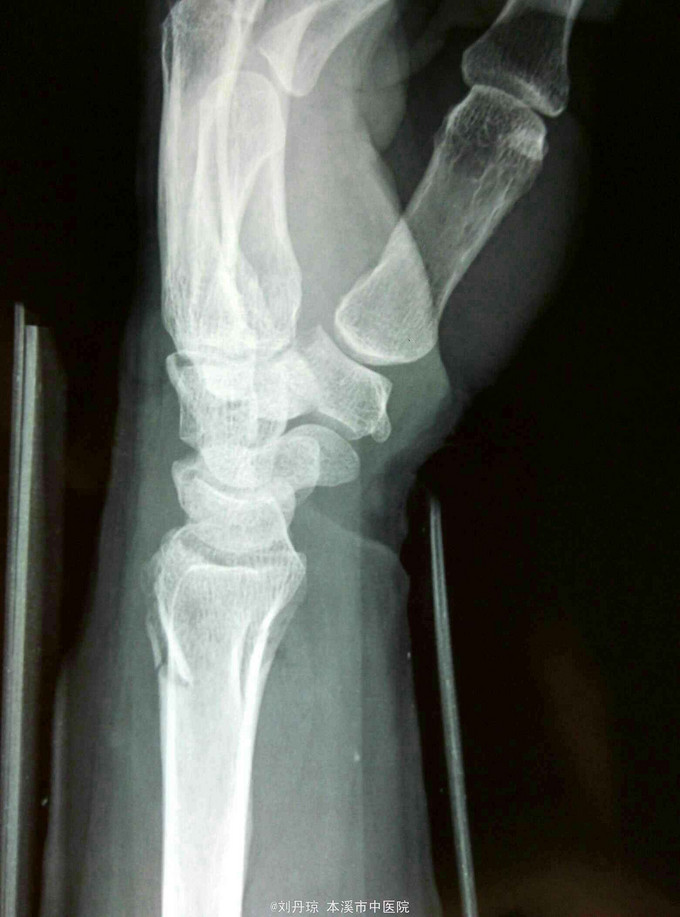

主诉:左腕刺痛,活动受限3小时。 病史: 患者3小时前不慎摔伤腕,伤后左腕刺痛,活动受限。遂来我院门诊求治。

诊断: 左colles骨折 治疗:手法整复,夹板固定,中药外用,接骨续筋中药口服。

随访|年。摔倒时腕关节极度背伸,使前臂旋前的扭力向前运动,导致此型骨折。colles 骨折占前臂骨折的75%,多见于中老年女性。colles骨折是最常见的骨折。典型表现为餐叉状畸形。主要包括然后远端向背侧移位和倾斜,桡偏,桡骨短缩,骨折常涉及桡腕关节和下尺桡关节。尺骨茎突骨折也是常见的合并损伤。